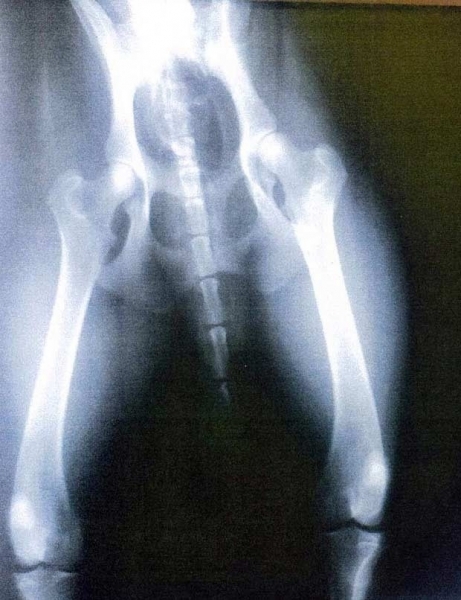

Médico é preso após confundir raio-X de cão com exame de paciente

O médico Rolando Lodevico foi preso na quinta-feira (12) nos Estados Unidos sob acusação de distribuir receitas médicas de forma imprópria.